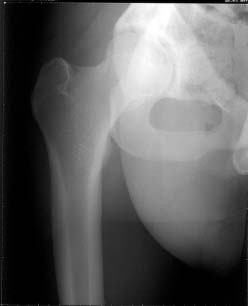

22 yrs man , semiprofessional( he earn some money from playing) basketball player got suffered in car accident.He had hip joint posterior luxation ( Pipkin 4) with little acetabular roof fragments ( nondisplaced) and anterosuperior abruption fracture of the head of the femur.

Additional injuries were severe face wounds. Emergency manipulations were reposition of the hip luxation under the radiologic control and wounds care. After reposition the CT scan was made. We found 2x3cm wide and 0.5 thick OCH fragment outside the joint surfaces , under the caput. The traction was applied.

Here are the missing postreduction views.